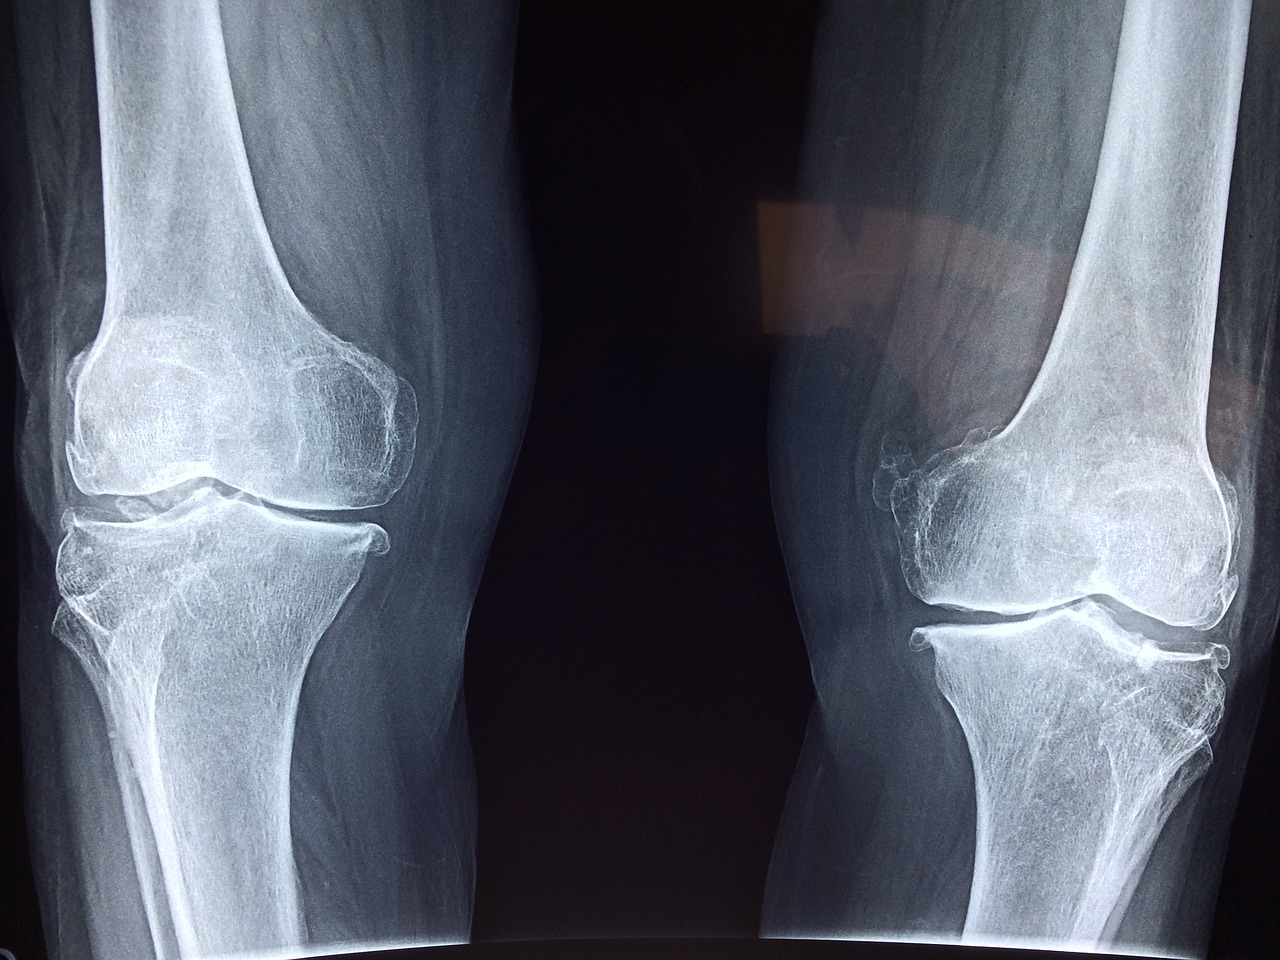

골밀도는 뼈의 강도를 수치로 나타내는 지표이며, 우리 몸을 지탱하는 골격 건강의 핵심 요소다. 특히 중년 이후 골밀도는 자연스럽게 감소하며, 이를 방치할 경우 골다공증과 같은 질환으로 이어질 수 있다. 문제는 골밀도 저하가 조용히 진행되며 자각 증상이 늦게 나타난다는 점이다. 본 글에서는 골밀도가 낮아질 때 몸에서 보내는 주요 신호들을 정리하고, 조기 대응의 중요성과 예방을 위한 기초 루틴을 함께 소개한다. 뼈 건강은 알고 관리할 때 지킬 수 있다.

골밀도는 일정 수준 이하로 낮아지기 전까지 자각 증상이 거의 나타나지 않는다. 이 때문에 '조용한 질환'이라고 불리며, 많은 이들이 골다공증 진단을 받은 후에야 뼈가 약해졌다는 사실을 인지하게 된다. 초기에는 다음과 같은 경미한 증상들이 나타날 수 있다. 첫째, 등이 자주 아프거나 뻐근함을 느낀다. 이는 척추 뼈의 미세 손상이나 압박골절 초기 현상일 수 있다. 둘째, 이유 없이 키가 줄어드는 경우다. 척추 뼈가 눌리면서 체간이 짧아지는 현상이 발생한다. 셋째, 손목이나 발목처럼 일상적으로 잘 쓰는 부위에 미세한 통증이 반복될 수 있다. 이는 뼈의 강도가 약해지면서 미세 골절 가능성이 높아졌다는 신호일 수 있다. 또한, 잦은 근육통이나 관절 통증으로 병원을 찾았다가 검사 중 우연히 골밀도 감소를 발견하는 경우도 많다. 손톱과 발톱이 쉽게 깨지거나, 치아 흔들림이 생기는 것도 뼈 건강 악화의 간접적인 신호일 수 있다. 이처럼 증상이 명확하지 않지만 반복되거나 일상 기능에 영향을 미칠 경우 정형외과 전문의의 검사를 받아보는 것이 좋다.

골밀도가 낮아지는 원인은 매우 다양하며, 연령, 성별, 생활 습관, 유전 요인 등이 복합적으로 작용한다. 가장 큰 원인은 나이다. 특히 폐경 이후 여성은 에스트로겐 감소로 인해 뼈 흡수 속도가 빨라지고, 골밀도가 급격히 낮아질 수 있다. 남성도 50대 이후부터 점차 뼈의 밀도가 줄어드는 경향이 있다. 식습관 역시 큰 영향을 미친다. 칼슘과 비타민 D 섭취가 부족한 경우, 뼈 형성과 유지에 필요한 재료가 부족해지며 골감소증이 진행될 수 있다. 또한 과도한 카페인, 알코올, 염분 섭취는 체내 칼슘 배출을 촉진시켜 골 손실을 가속화시킨다. 흡연 역시 뼈세포의 활동을 저해해 골밀도 감소에 영향을 준다. 운동 부족도 중요한 요인이다. 특히 체중 부하 운동(걷기, 등산, 웨이트 트레이닝 등)을 하지 않으면 뼈에 자극이 줄어들어 골량 유지가 어려워진다. 유전적인 요인, 갑상선 질환, 류머티즘 관절염, 스테로이드 장기 복용 등도 뼈 건강을 해치는 요인으로 알려져 있다. 위험군에 속하는 사람이라면 정기적으로 골밀도 검사를 받는 것이 중요하다. 특히 폐경기 여성, 65세 이상 고령자, 골절 병력이 있는 사람, 장기간 약물 치료를 받는 환자 등은 선제적 관리가 필요하다.